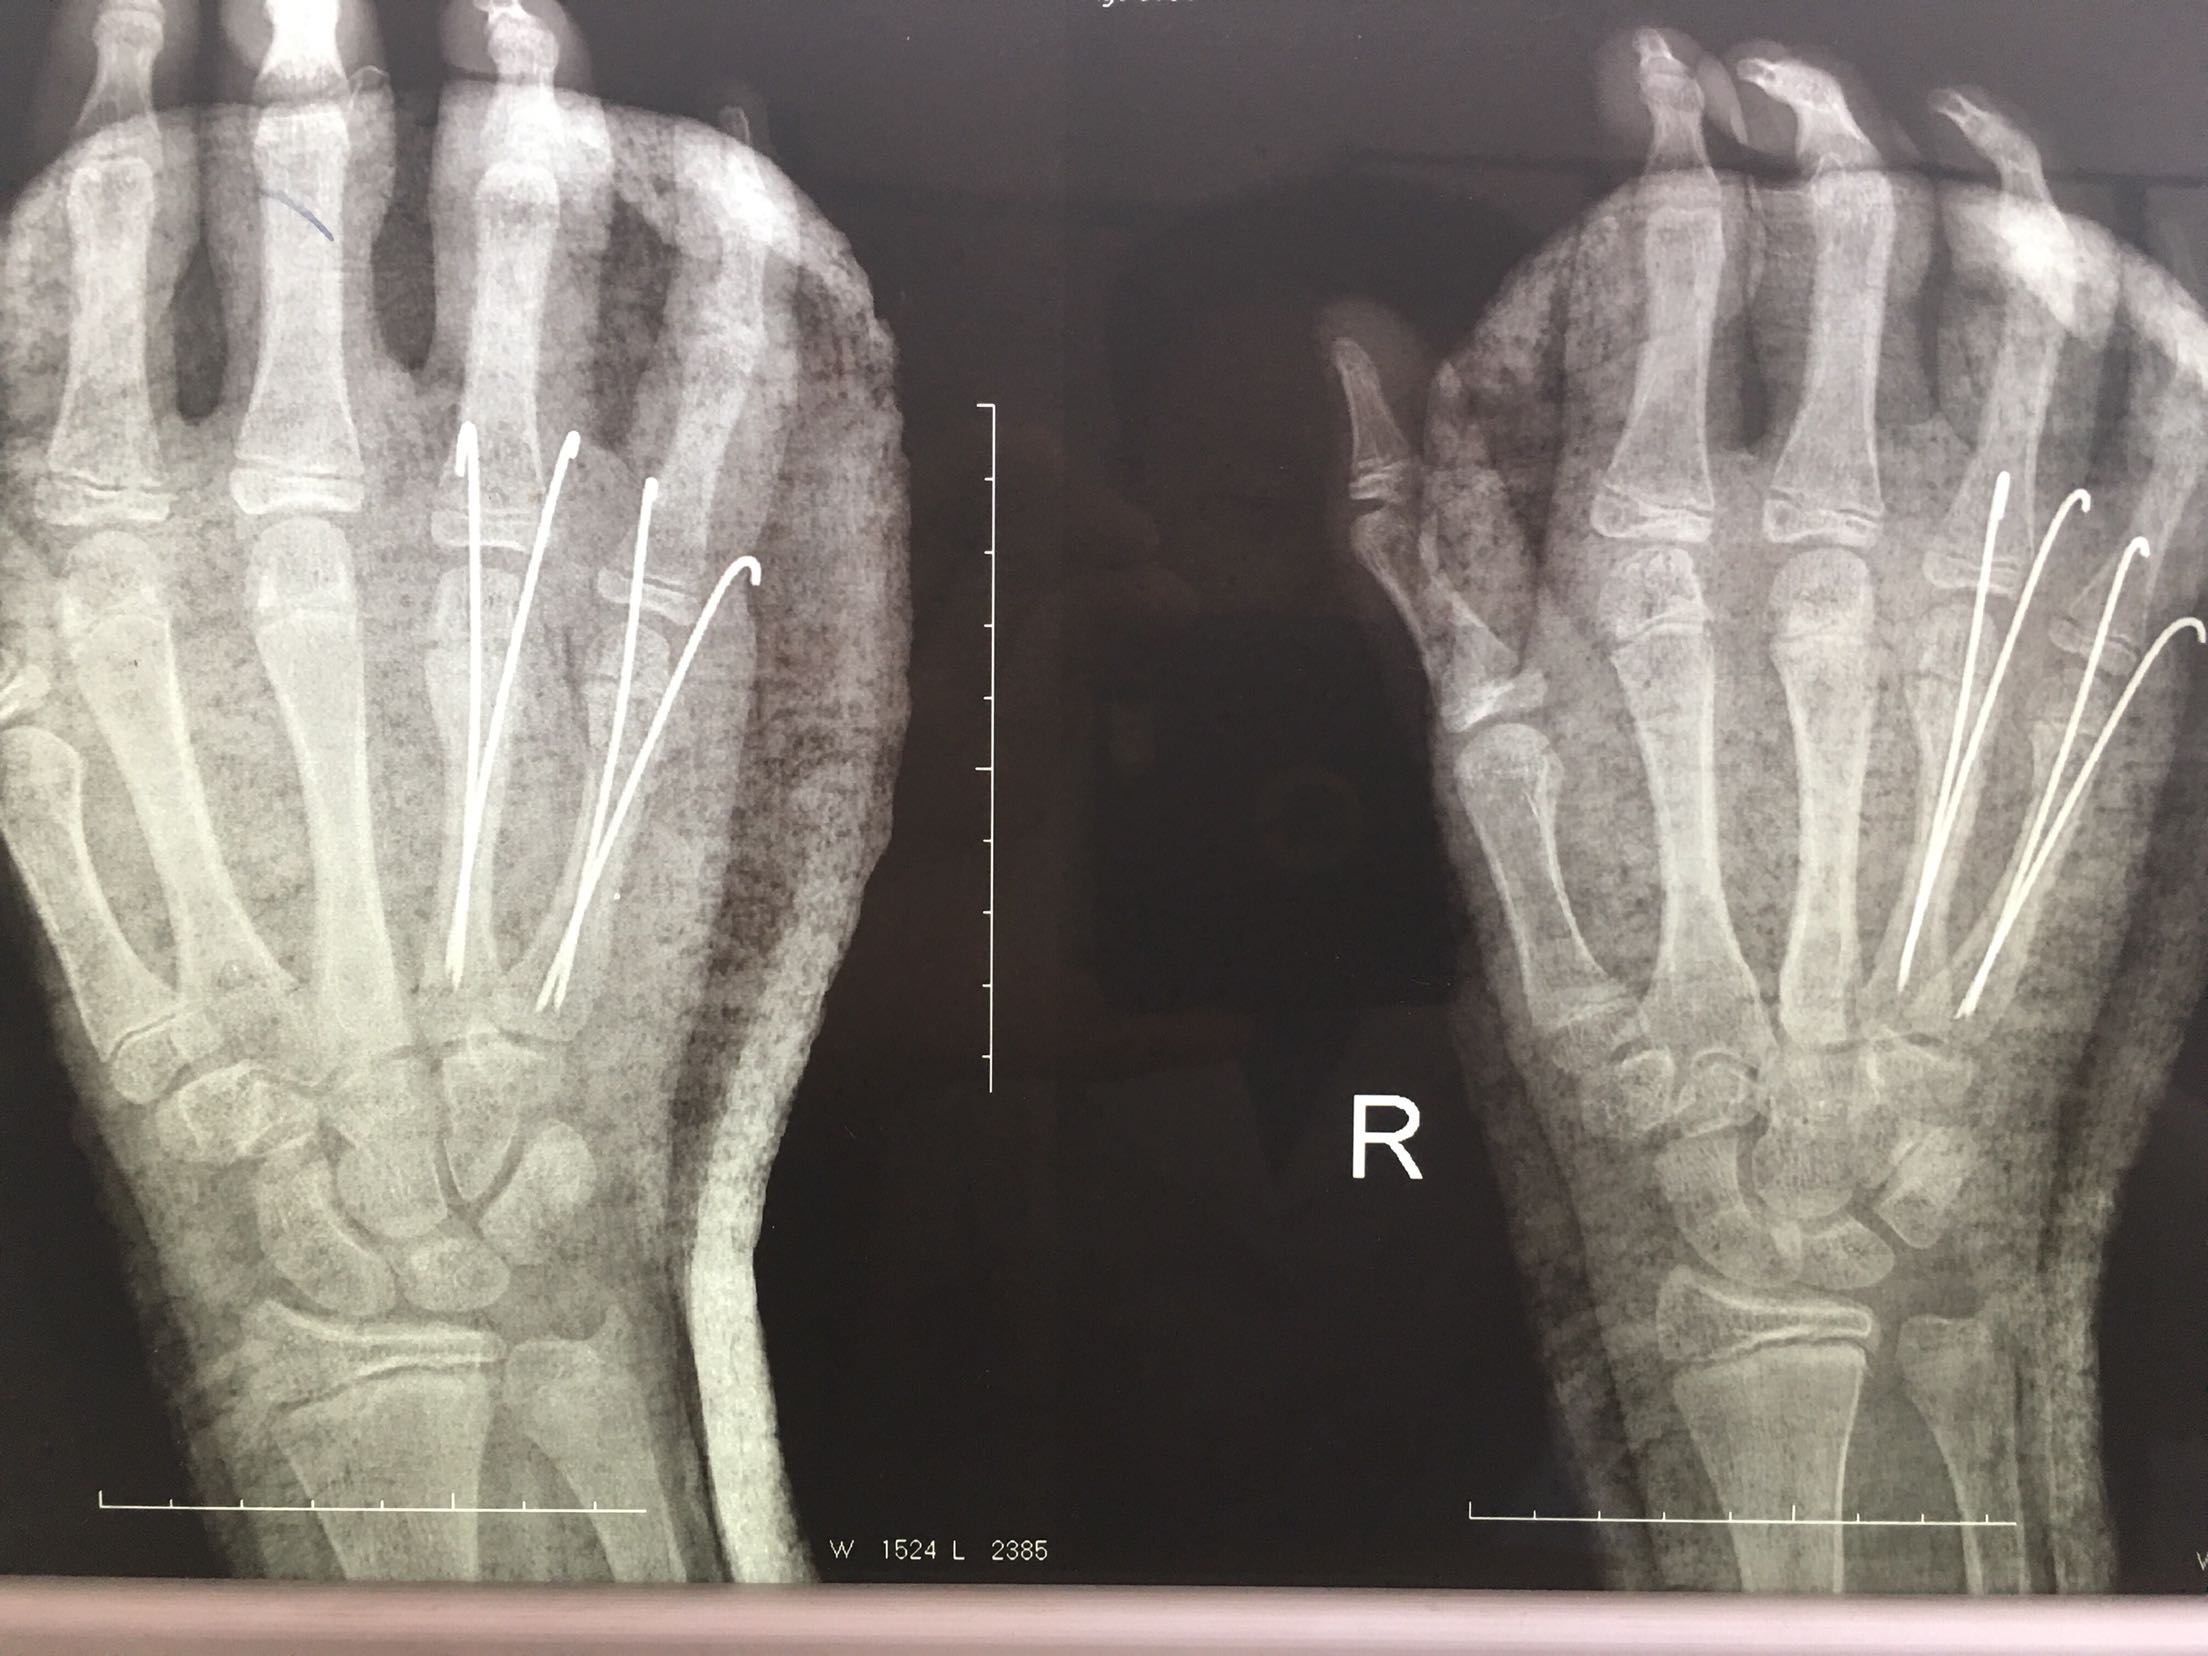

右第四,五掌骨骨折(微创)

完善检查,在臂丛麻醉下行闭合复位内固定术,术后抗炎,消肿止痛等对症处理,右手石膏托制动。